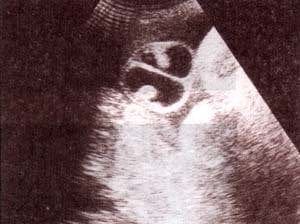

fig. 91. – (a). siameses toraco-onfalópagos corte transversal a nivel del torax. las cavidades cardíacas se encuentran unidas. |

fig. 91.– (b). corte transversal a nivel abdominal. hay unión clara compartiendo hígado. |